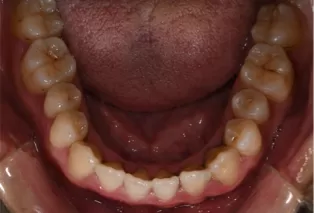

Intraoral photos after treatment